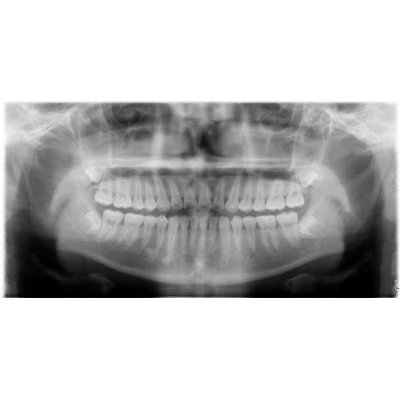

兒童牙科

人工植牙